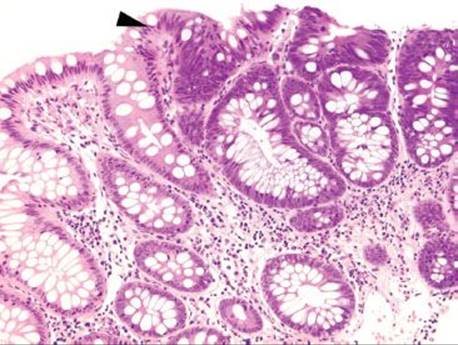

Figure 4.272 Endometriosis. Higher power shows convoluted glands surrounded by a cuff of stroma cells and intermixed lymphoid cells.

Figure 4.273 Endometriosis. Higher power of previous image. Cilia are not definitively identified in this suboptimal specimen. Biopsies of the lesion had raised concerns for an infiltrating adenocarcinoma because the glandular elements were not recognized as endometrial, the overlying reactive changes were interpreted as dysplasia, and numerous mitotic figures were seen.

Endometriosis is the presence of at least two of the three following features outside of the uterus: endometrial glands, stroma, and hemorrhage (Figs. 4.271–4.273). Up to 37% of women with endometriosis have intestinal involvement, and any layer of the bowel can be involved. The clinicopathologic presentation is diverse and presentations can overlap with appendicitis, IBD, diverticular disease, infectious colitis, a surgical acute abdomen, malignancy.125–128 Endometriosis involving the rectum commonly presents as bloody diarrhea. Associated pathologic findings can include strictures, ulceration, fissures, ischemia, and intussusception.125 The lesions can appear as polyps or bleeding mass lesions, raising clinical concerns for malignancy. The overlying colonic epithelium can be markedly reactive and mimic dysplasia, leading to the misdiagnosis of colonic adenocarcinoma. Occasionally, only the stromal component is seen and a diagnosis of sarcoma is entertained. In these cases, usually the endometrial glands can be identified on deeper sections. Confirmatory immunohistochemical stains include ER and PR to highlight the glandular components and CD10 to highlight the endometrial stroma.